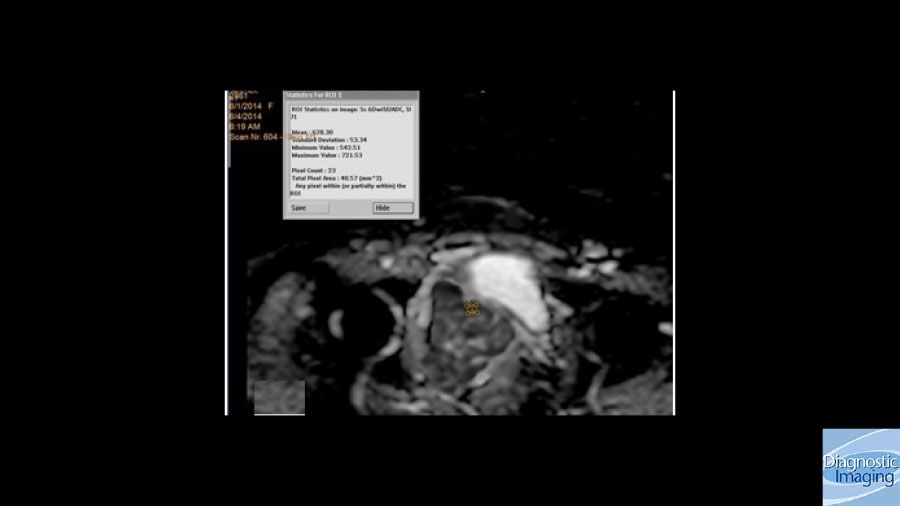

Case History: 60-year-old female presented with postmenopausal bleeding and pelvic pain.